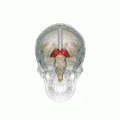

Thalamus

![]() Visual depiction of basic thalamus | |

The thalamus (pl.: thalami; from Greek θάλαμος, "chamber") is a large mass of gray matter on the lateral wall of the third ventricle forming the dorsal part of the diencephalon (a division of the forebrain). Nerve fibers project out of the thalamus to the cerebral cortex in all directions, known as the thalamocortical radiations, allowing hub-like exchanges of information. It has several functions, such as the relaying of sensory and motor signals to the cerebral cortex[1][2] and the regulation of consciousness, sleep, and alertness.[3][4]